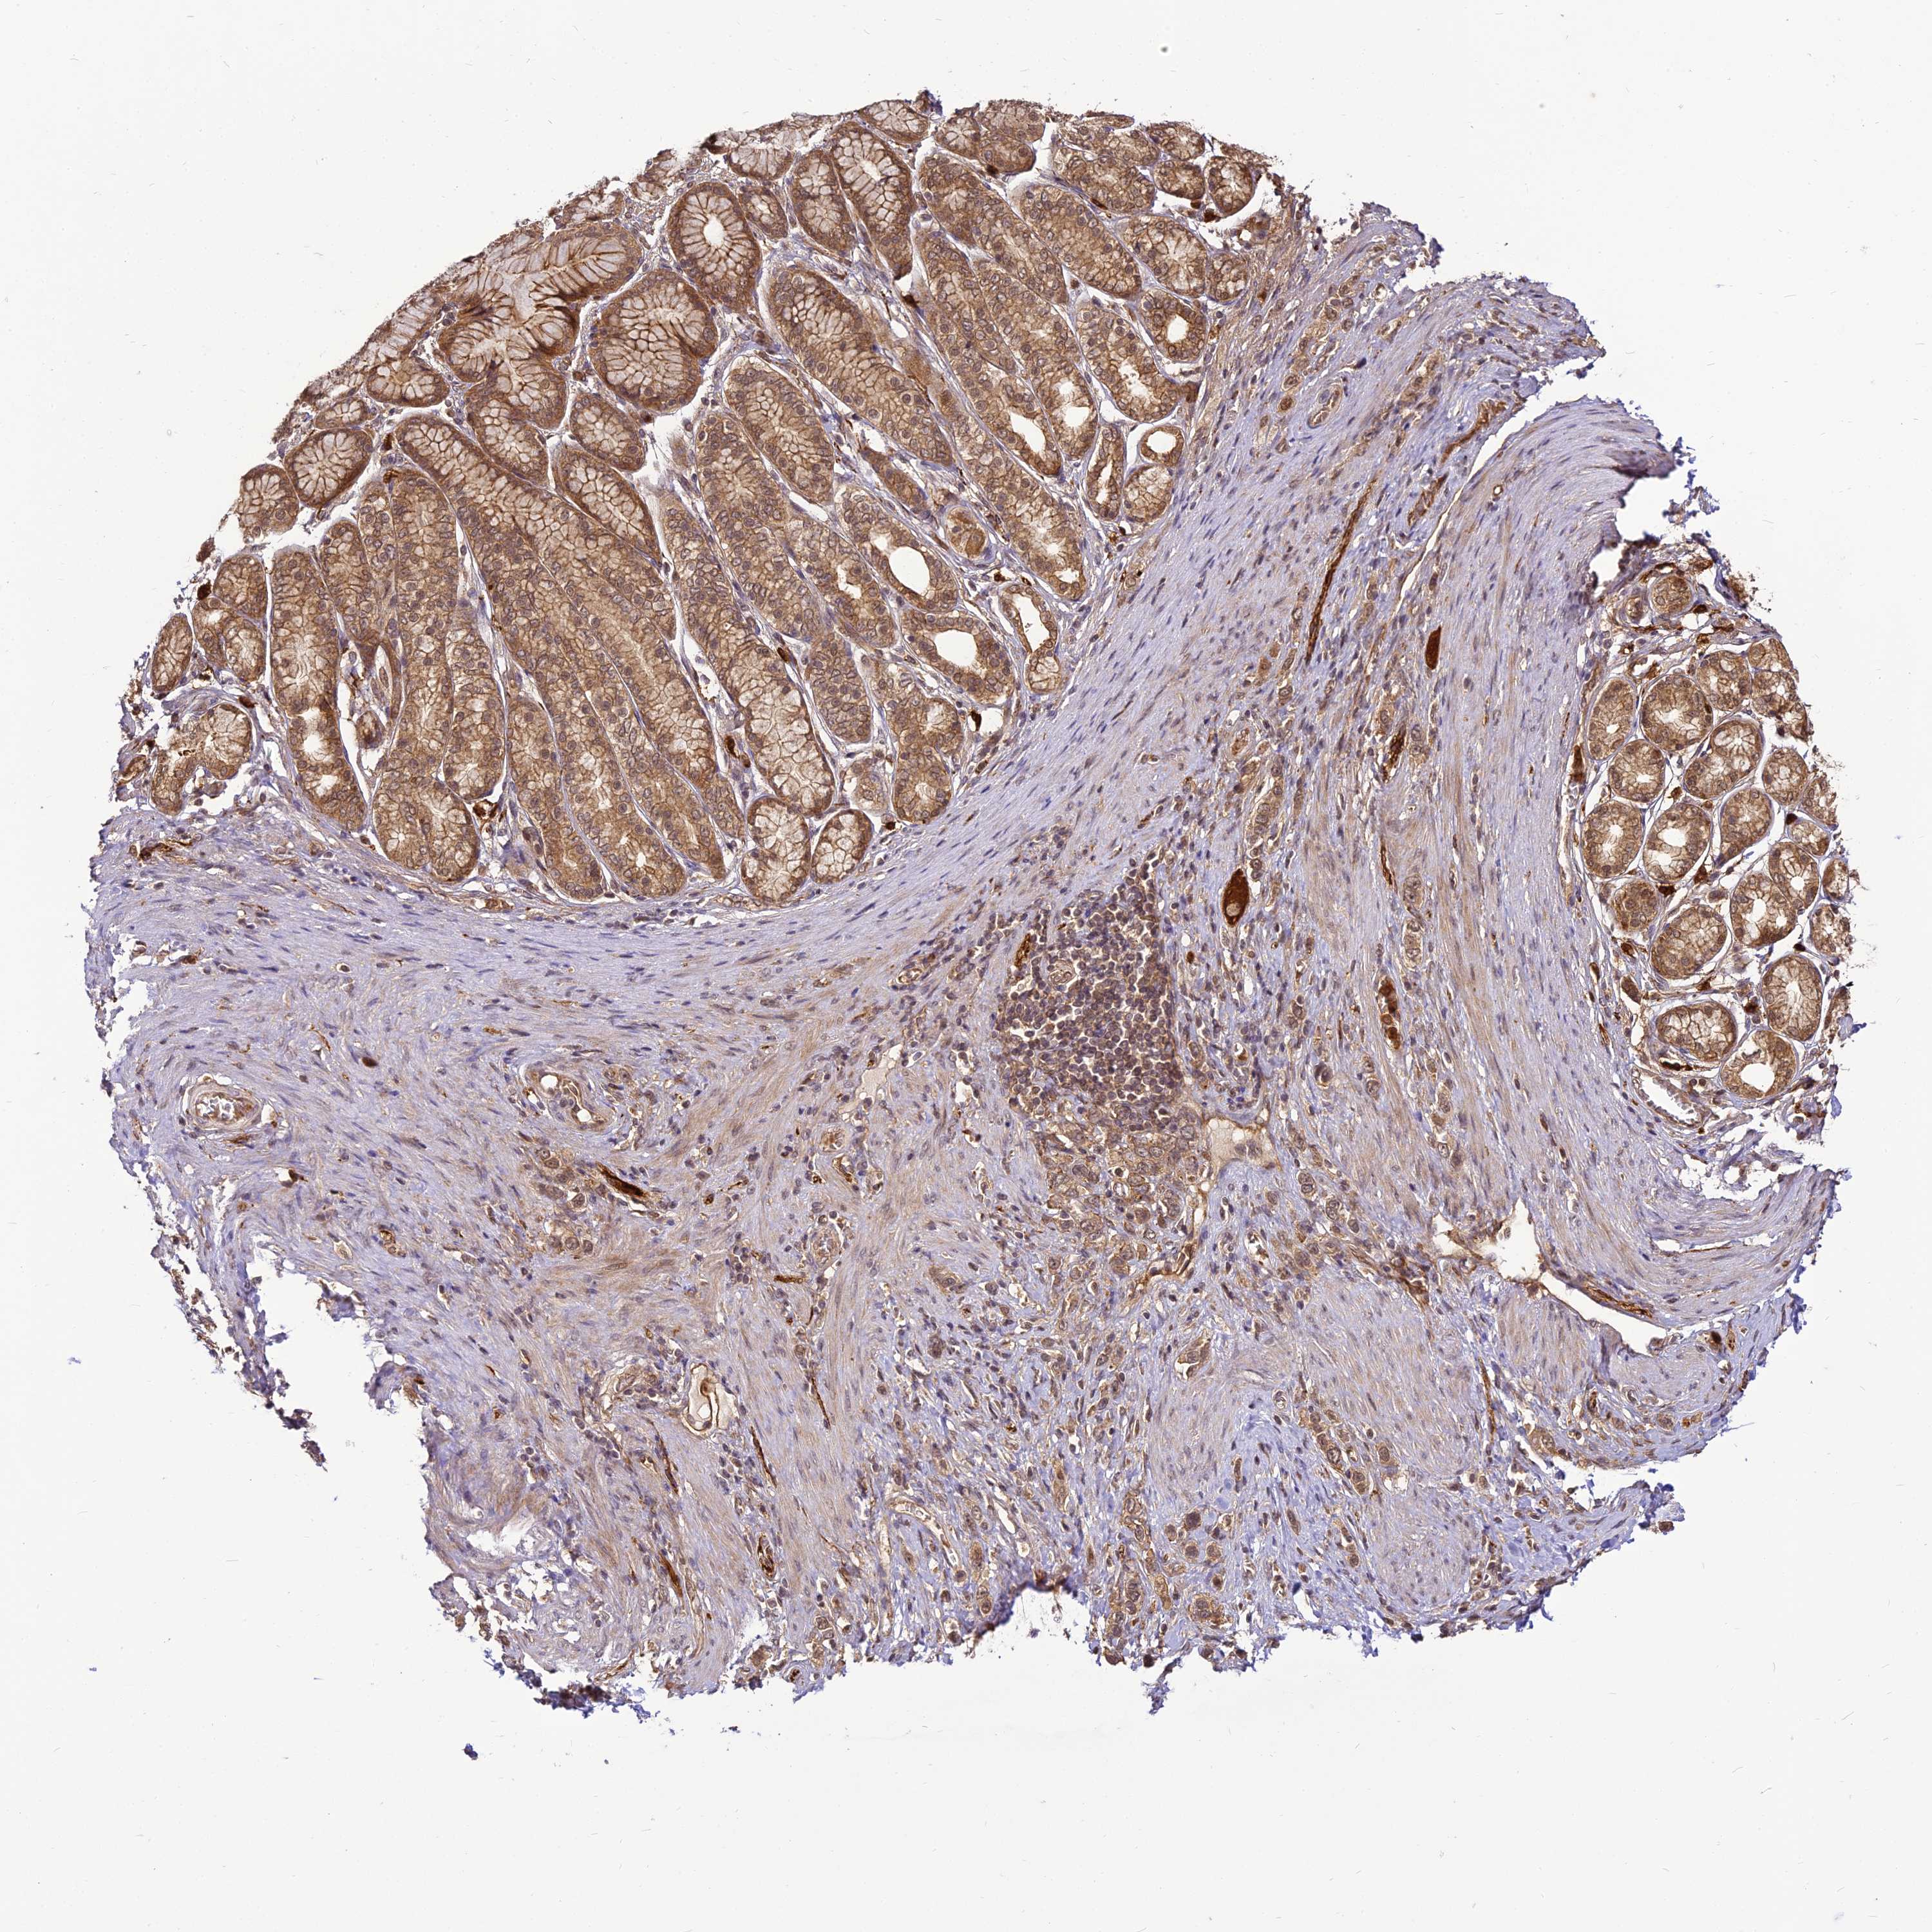

STOMACH CANCER - Protein expressioni

A mouse-over function shows sample information and annotation data. Click on an image to view it in a full screen mode. Samples can be filtered based on level of antibody staining by selecting one or several of the following categories: high, medium, low and not detected. The assay and annotation is described here.

Note that samples used for immunohistochemistry by the Human Protein Atlas do not correspond to samples in the TCGA dataset.

Antibody stainingi

Antibody staining in the annotated cell types in the current human tissue is reported as not detected, low, medium, or high, based on conventional immunohistochemistry profiling in selected tissues. This score is based on the combination of the staining intensity and fraction of stained cells.

Each image is clickable and will lead to virtual microscopy that enables deeper exploration of all samples and also displays staining intensity scores, fraction scores and subcellular localization as well as patient and tissue information for each sample.

Antibody HPA039911

Staining

High

Medium

Low

Not detected

Intensity

Strong

Moderate

Weak

Negative

Quantity

>75%

75%-25%

<25%

None

Location

Nuclear

Cytoplasmic/membranous

Cytoplasmic/membranous,nuclear

Adenocarcinoma, NOS